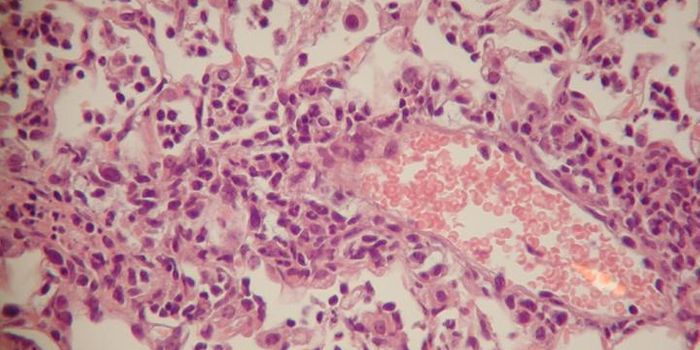

MAY 21, 2018CancerThe malarial parasite expresses a protein, VAR2CSA, that binds to chondroitin sulfate (CS) found on both placental and c ...